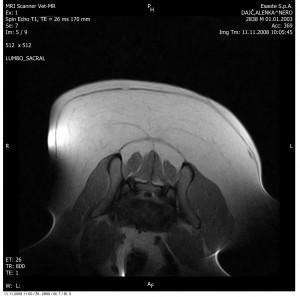

Slika: Primer zdrsa medvretenčnega diska v ledvenokrižnem področju